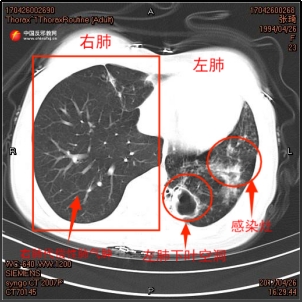

During her second tuberculosis diagnosis in April 2018, sputum cultures confirmed a co-infection of Aspergillus fumigatus. Dr. Zhang Yang, her resident physician at the time, recalled the challenges of her treatment, "Zhang Qi’s second diagnosis was relapsed multi-drug-resistant tuberculosis (MDR-TB). We developed a targeted treatment plan and added oral antifungal medication." Chest CT scans taken over the course of her treatment documented the deterioration of her left lung, the cavitation in the lower lobe of the left lung was expanding, the lung lobe was atrophying, and the infection was progressively worsening.

▲ Left: Chest CT scan of Zhang Qi from April 2017; Right: Chest CT scan from April 2018.